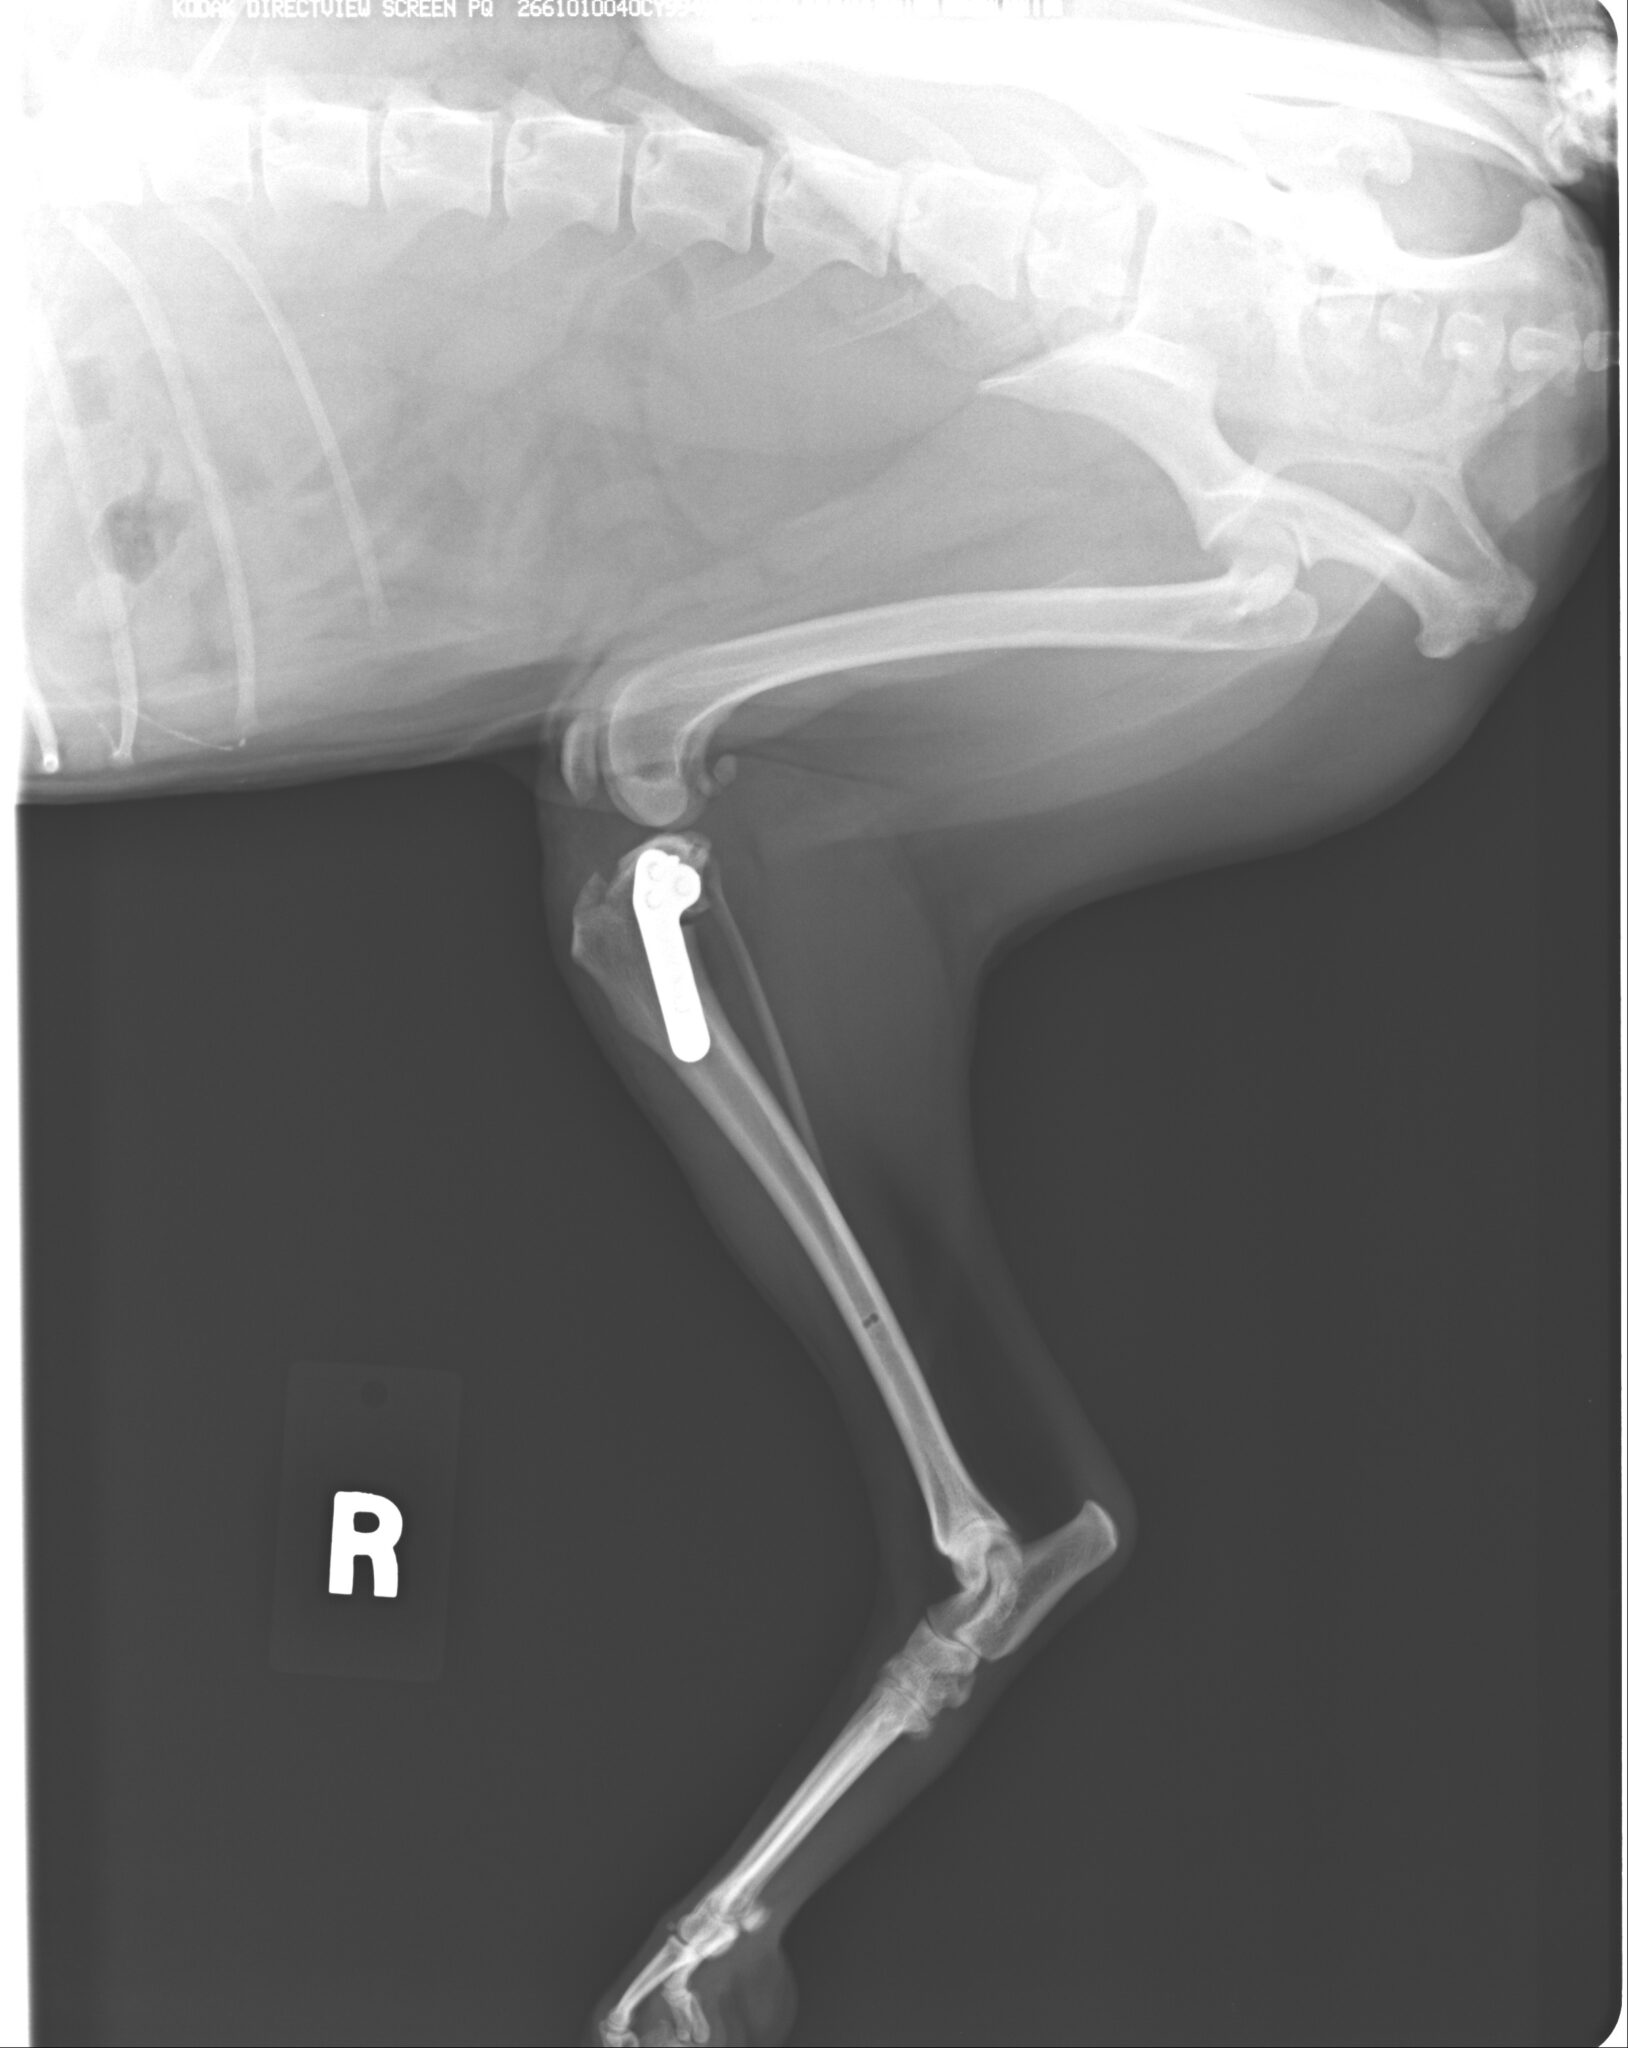

前腕骨骨折整復(ロッキングシステム)

強固かつ骨折修復過程に必要な組織を温存させた手術は治癒過程が早く、早期に運動を再開できます

強固かつ骨折修復過程に必要な組織を温存させた手術は治癒過程が早く、早期に運動を再開できます

小型犬ほど骨折が多く、治癒しにくいため、インプラントの選択が重要になってきます

大型犬の外傷性骨折はとても少なくなってきましたが、しっかりと対応しています

高所からの落下など骨端部骨折は少なくありません。端の手術のため難易度が高くなります。

ダブルプレートによる強固な内固定ではピンニングと比べると、早期に歩行が可能になります

骨切りを行う前にインプラントの適応など入念な手術計画が必要です